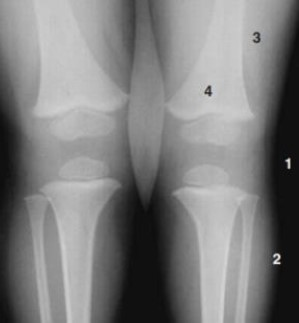

Analise a figura.

Fonte: JUNIOR, C. M., Radiologia Básica, 2 ed., Revinter, 2016.

Quais das numerações presentes na figura, refere-se ao ar e à gordura, respectivamente?